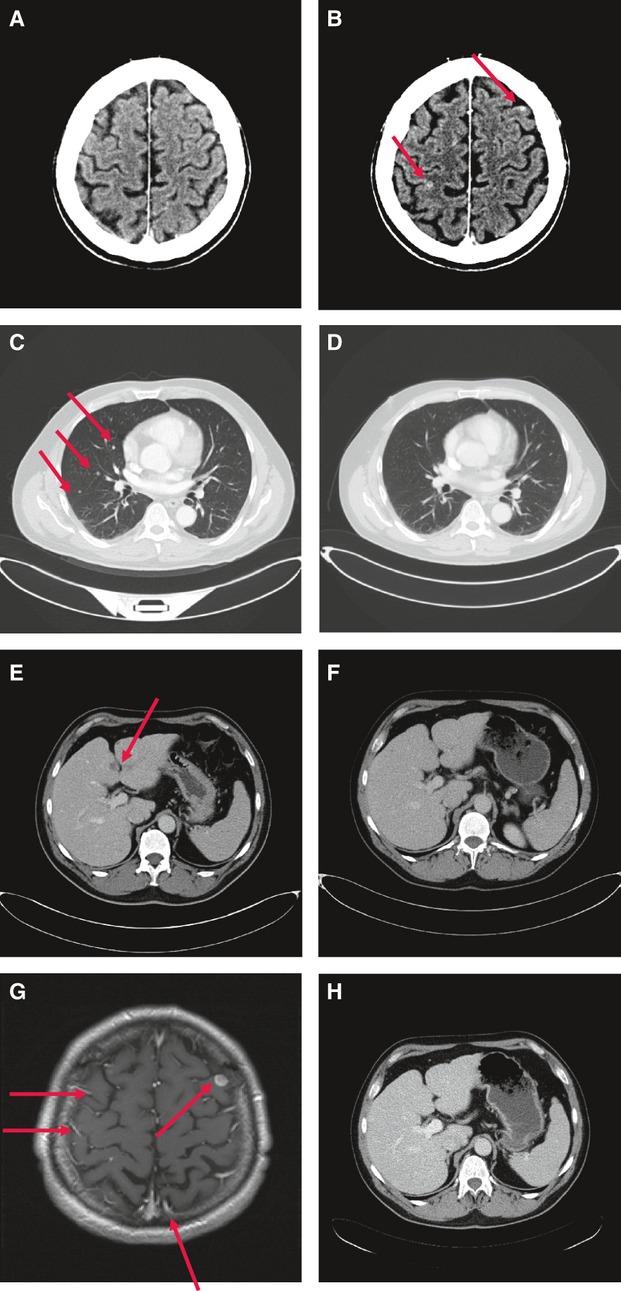

Brain metastases are the most common cause of death in patients with metastatic melanoma, and the RAF-MEK-ERK and PI3K-AKT signaling pathways are key players in melanoma progression and drug resistance. The BRAF inhibitor vemurafenib significantly improved overall survival. However, brain metastases still limit the effectiveness of this therapy. In a series of patients, we observed that treatment with vemurafenib resulted in substantial regression of extracerebral metastases, but brain metastases developed. This study aimed to identify factors that contribute to treatment resistance in brain metastases. Matched brain and extracerebral metastases from melanoma patients had identical ERK, p-ERK, and AKT immunohistochemistry staining patterns, but there was hyperactivation of AKT (p-AKT) and loss of PTEN expression in the brain metastases. Mutation analysis revealed no differences in BRAF, NRAS, or KIT mutation status in matched brain and extracerebral metastases. In contrast, AKT, p-AKT, and PTEN expression was identical in monolayer cultures derived from melanoma brain and extracerebral metastases. Furthermore, melanoma cells stimulated by astrocyte-conditioned medium showed higher AKT activation and invasiveness than melanoma cells stimulated by fibroblast-conditioned medium. Inhibition of PI3K-AKT signaling resensitized melanoma cells isolated from a vemurafenib-resistant brain metastasis to vemurafenib. Brain-derived factors appear to induce hyperactivation of the AKT survival pathway and to promote the survival and drug resistance of melanoma cells in the brain. Thus, inhibition of PI3K-AKT signaling shows potential for enhancing and/or prolonging the antitumor effect of BRAF inhibitors or other anticancer agents in melanoma brain metastases.